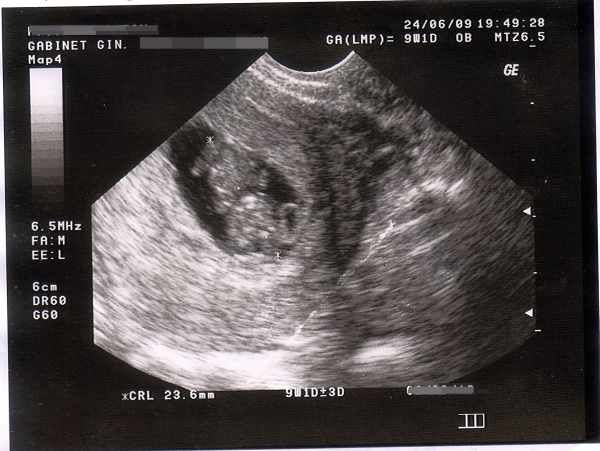

Była pierwsza wizyta u lekarza, pierwsze wyczekiwane USG i poczynione drobne zakupy dla maluszka.